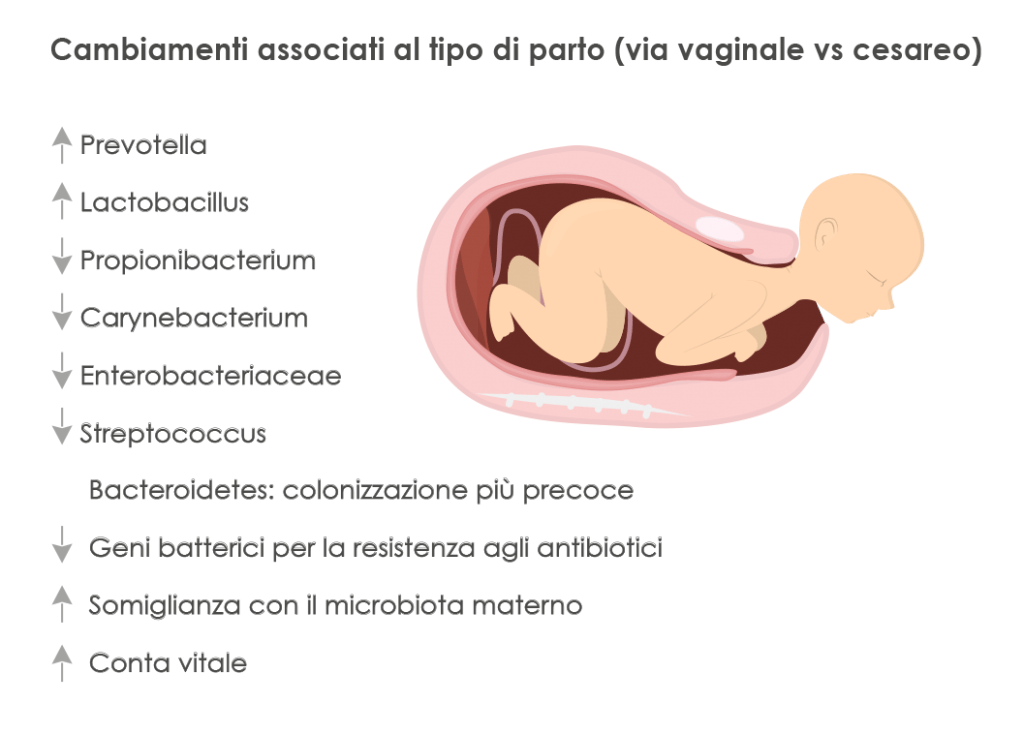

Microbioma, gravidanza e allattamento